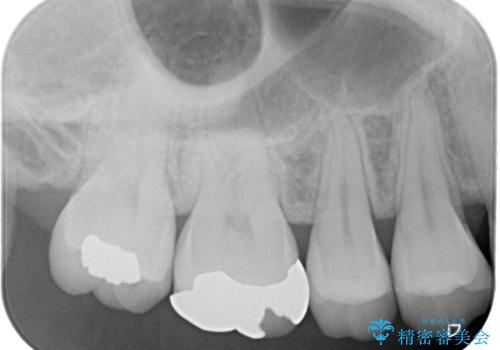

右上の6番目の歯はメタルインレーが大きかったためルジルコニアクラウン、右上の7番目の歯は一番奥で審美的な要素よりも機能面を重視してゴールドインレー修復による治療計画を立案しました。

拡大鏡視野下で保険のプラスチック(コンポジットレジン)、虫歯を除去し、フルジルコニアクラウン、ゴールドインレーに適した形にしました。